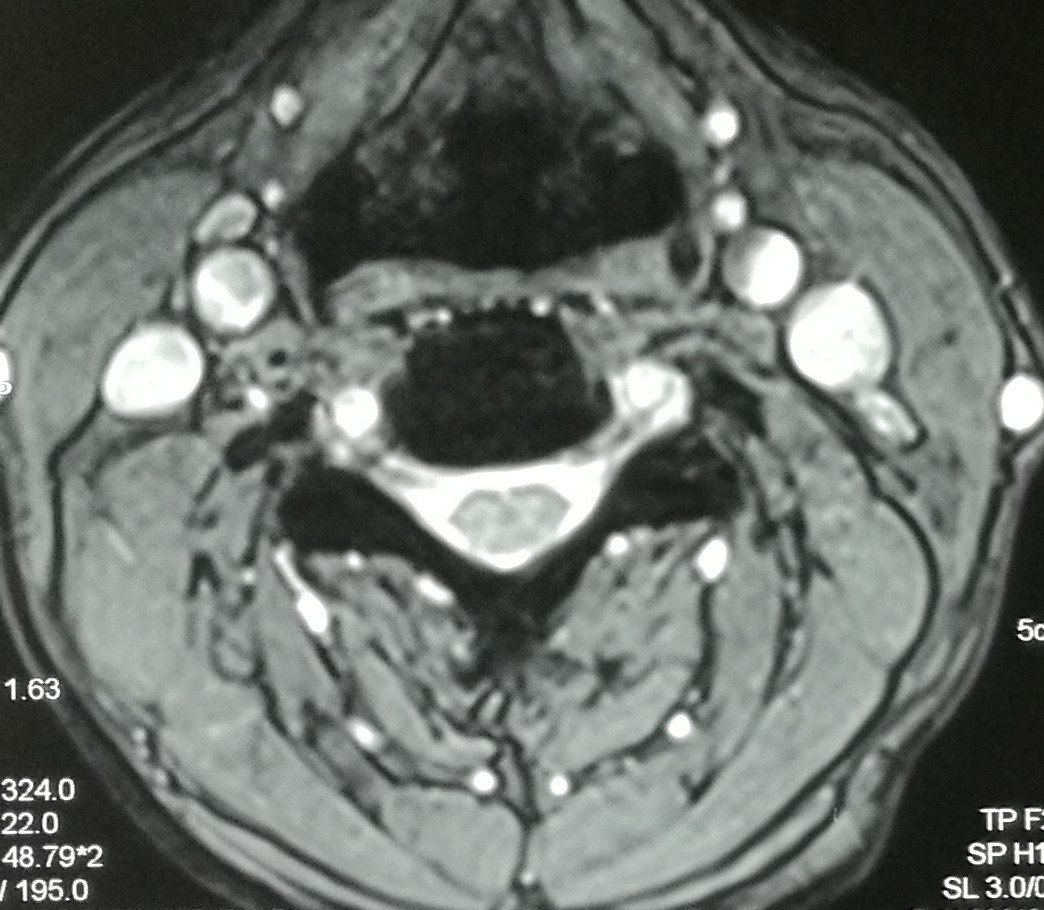

②脊髓型颈椎病的患者,症状主要表现双侧上肢疼痛麻木,无力,拿东西困难容易掉,走路无力,有踩棉花感。颈椎MRI显示:颈椎间盘突出,压迫脊髓导致局部椎管狭窄,白色脑脊液消失(图5—1)。而正常颈椎椎管可见脊髓漂浮在脑脊液内(图5—2)。